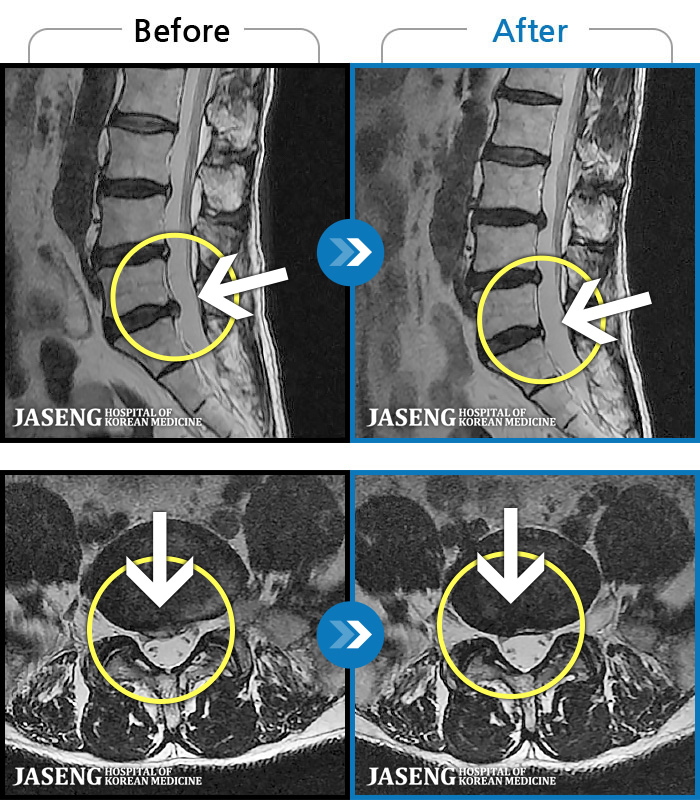

50 MRI ũ ʸ Ȯϼ.